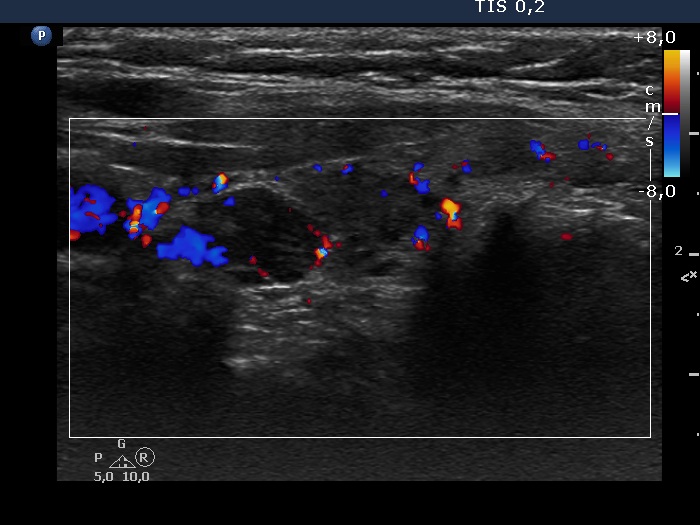

Left lobe, longitudinal scan, color Doppler mode. The vascularization is average.